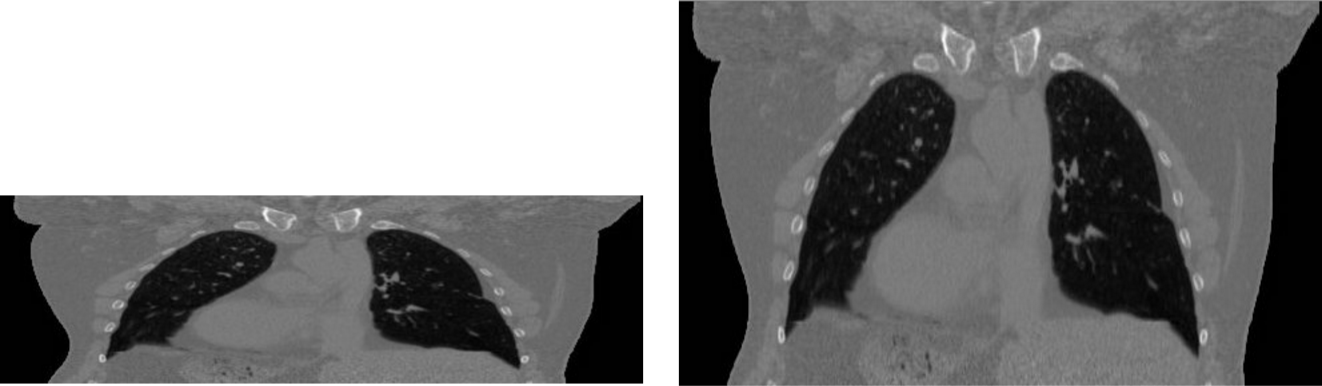

为了强调此处的图像不仅仅是一个数字组成的矩阵,用图说话

两幅图的内容能看出来是一样的,但是像素间距不同